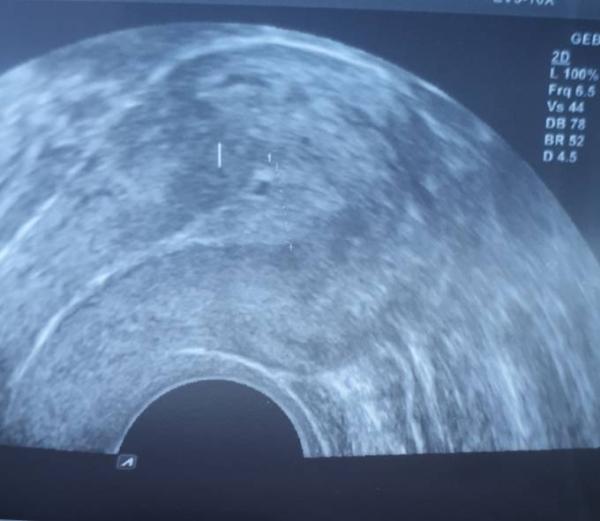

Hallo Hab seit gestern Blutungen. War beim Fa. Schleimhaut ist im Vergleich zu Montag größer geworden und die Blase ist auch besser sichtbar gewesen Wenn ich das US Bild so anschaue, sehe ich seitlich hamatom. Woher die Blutungen kommen konnte der Fa nicht sagen

Bild zu Seit gestern Blutungen - Forum für Januar - Mamis

Oh mist, sind die Blutungen denn noch doll? Ich sehe kein Hämatom. Hat der FA nichts gesehen? Ruh dich vielleicht ein bisschen aus. Ich drücke dir die Daumen!